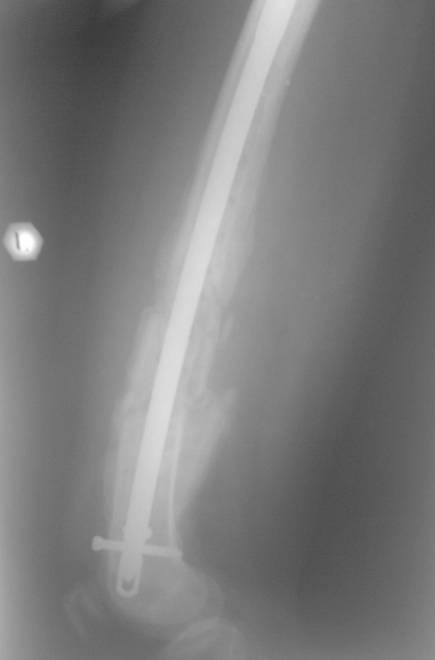

[Ortho] Несращение бедра

На сегодняшний момент (2 месяца после операции). Больная передвигается

при помощи трости из-за чувства неуверенности и ощущения онемения в

подколенной ямке. В квартире передвигается без дополнительной опоры.

Возникли вопросы по дальнейшей тактике ведения такой больной:

1. Удалять ли статический винт? Сроки? Способ?

2. Причины и возможные методы лечения индуративного отека н/3 бедра?